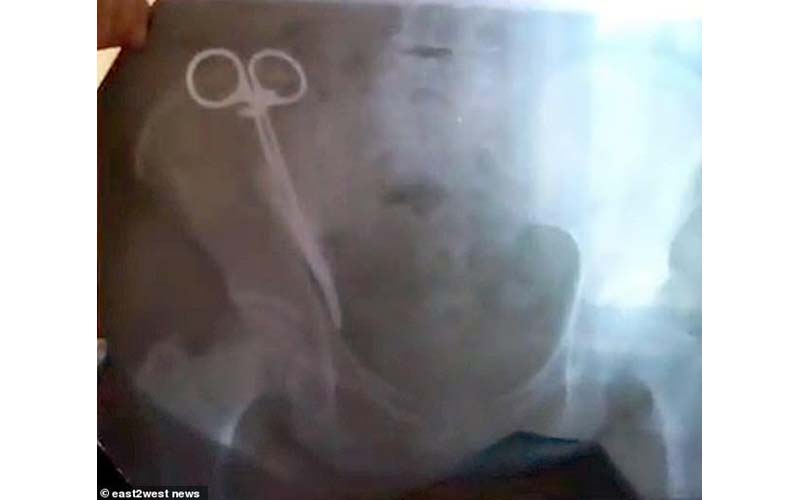

بعد 23 عامًا من إجرائها عملية قيصرية..امرأة تكتشف مقصًا في بطنها (صور)

عاشت 23عاماً تحمل بين احشائها مقصاً معدنيا بعد إجراء عملية قيصرية في أحد مستشفيات روسيا.

حسبما ذكرت صحيفة "ديلي ميل" البريطانية، كانت إيزيتا جوبييفا، 62 عامًا، قد شعرت منذ أيام بآلام حادة في بطنها، وتم تشخيص حالتها من جانب الأطباء بوجود مشاكل في الكبد ووصفوا لها أدوية ومسكنات آلام دون جدوى حيث استمر الالم ولم تجدى الادوية نفعاً،ولم يجد الأطباء بدا من طلب إجراء أشعة سينية على البطن أظهرت وجود مقص معدنى طوله ست بوصات على الأقل، وأمام حيرة الأطباء عن الجسم المعدنى داخل احشائها أبلغتهم "جوبييفا"أنها كانت قد أجرت إيزيتا عملية قيصرية في عام 1996 بمنطقة شمال أوسيتيا